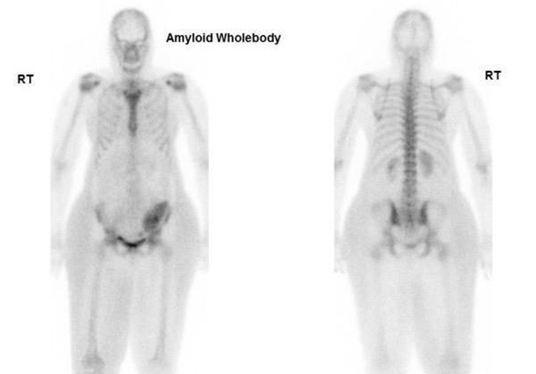

Case studies

The first case of a patient suspected of CA with a kidney transplant was referred to our nuclear medicine department at Guy's and St Thomas' Hospital. The DPD whole-body planar imaging shows normal bone uptake and absent cardiac uptake. (Figure 7)

Figure 7 Demonstrating DPD bone scan of a patient undergoing cardiac amyloid study showing no cardiac uptake and normal bone uptake. Kindly contributed by Dr Charlotte Fowler, Guy's and St Thomas' Hospital.

The second case involved a suspected CA patient who was referred to our nuclear medicine department at Guy's and St Thomas' Hospital. The DPD whole-body planar imaging shows defused and attenuated bone uptake and Perugini Grade 2 cardiac uptake. (Figure 8)

Figure 8 Demonstrating DPD bone scan of a patient undergoing cardiac amyloid study showing intense cardiac uptake. Perugini Grade 2. Kindly contributed by Dr Hajira /lyas, Guy's and St Thomas' Hospital.